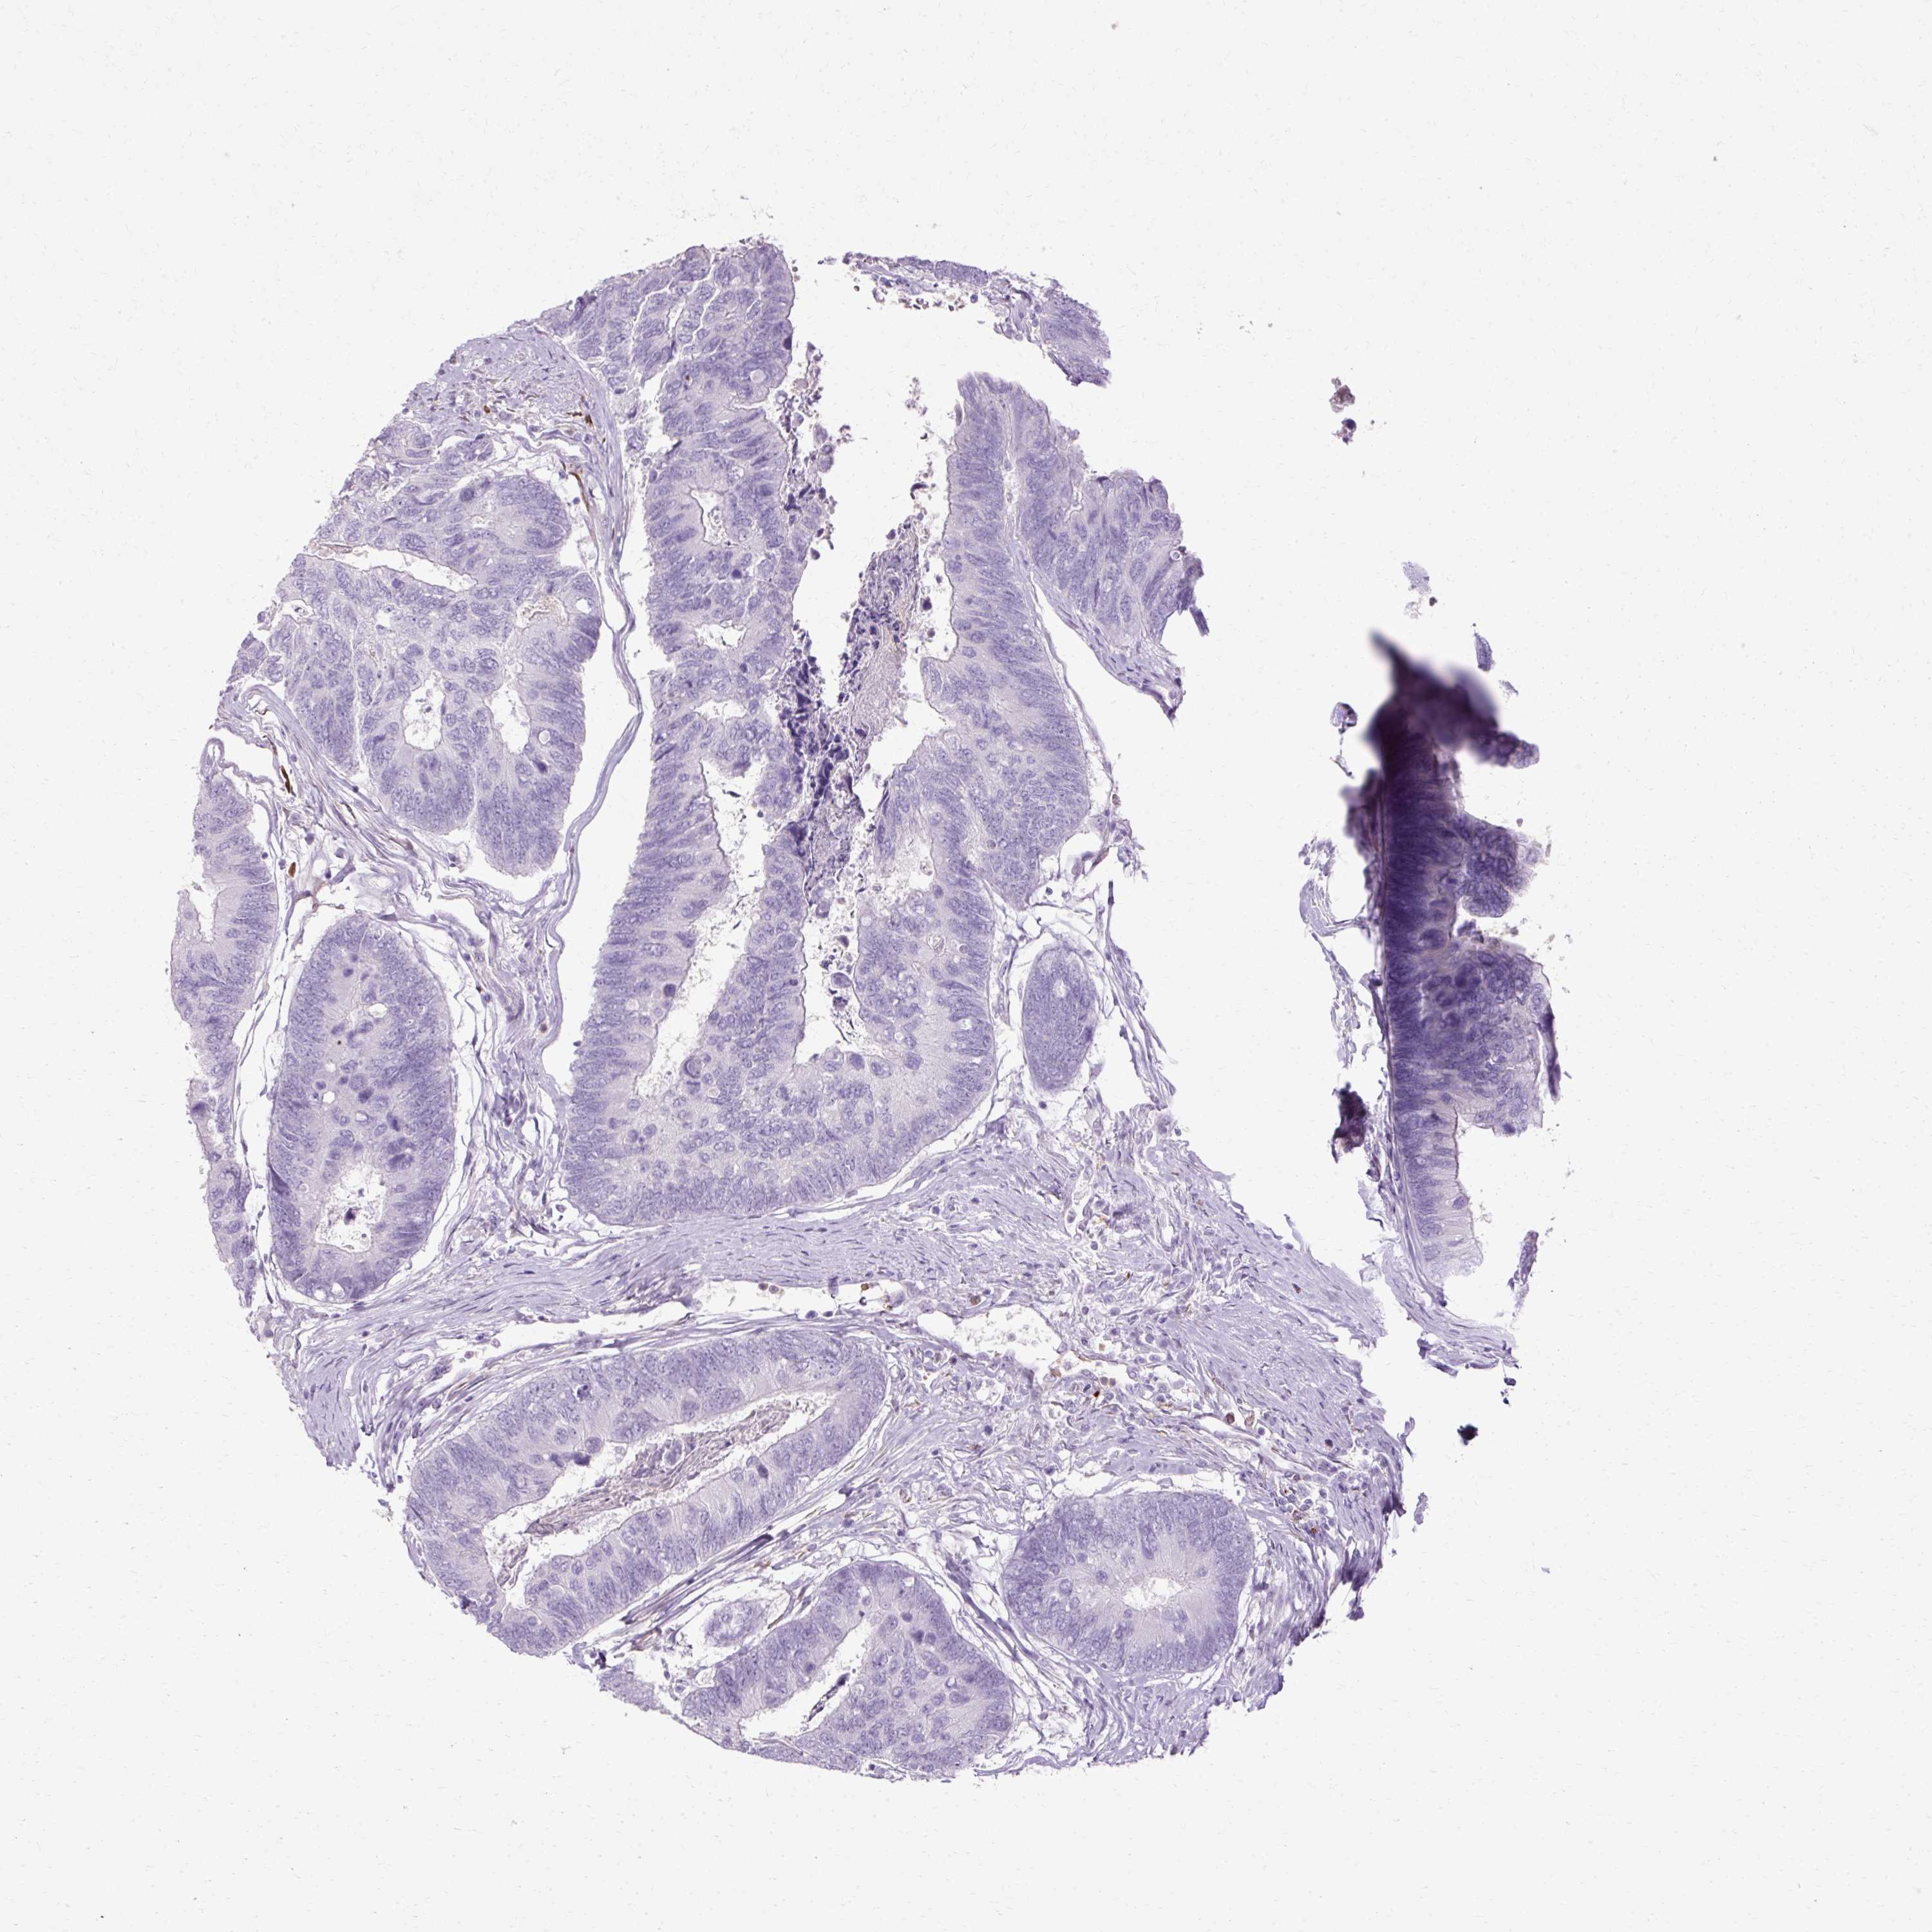

Colorectal cancer

Rectum adenocarcinoma

HSD11B1 is not prognostic in Rectum Adenocarcinoma (TCGA)